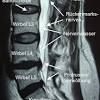

Bandscheibenvorfall Lws Hws Mrt Beta Klinik Bonn

Bandscheibenvorfall Lws Hws Mrt Beta Klinik Bonn from www.betaklinik.de